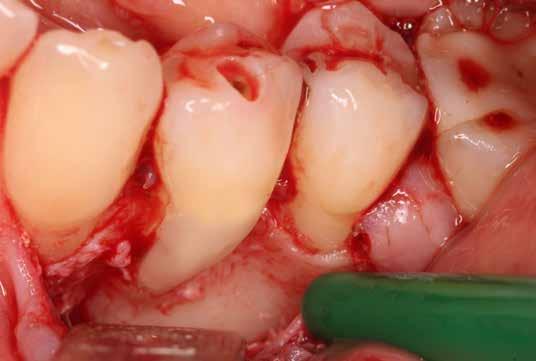

A megfelelő vizuális kontroll és az izolálhatóság kedvéért lebenyt alakítottunk [4. kép]. Így az abszolút izolálás már kivitelezhető volt és kofferdám izolálásban kezeltük a léziót [5. kép]. Mivel az elváltozás nem látható területen helyezkedett el, illetve a kavitás kis kiterjedését figyelembe véve kalcium-szilikát bázisú anyagot választottunk a restauráláshoz (Biodentine, Septodont) [6. kép]. Miután letelt a választott anyagunk kötési ideje (12 perc), zártuk a lebenyt [6. kép]. Páciensünk azóta is panaszmentes, kétéves kontrollon állapota rendben volt [7. és 8. kép].

Az üregben nagy mennyiségű gyulladásos szövetet találtunk, mely eltávolítása után láthatóvá vált a kavitás kiterjedése [13. kép]. A kisőrlő fogakra jellemző tengelyirányú, valamint oldalirányú terhelés kombinációja, valamint a jelentős foganyagveszteség miatt szerettük volna a lehető legjobban megerősíteni a fogat. A terület kofferdám gumilepedővel történő abszolút izolálása után a gyö-

kércsatornát egy guttapercha segítségével kiblokkoltuk, ezzel megelőzve a csatorna obliterálódását [14. kép]. Ezután megfelelő adhezív előkezelést követően kompozit tömőanyaggal restauráltuk az elváltozást (Essentia Universal, GC Europe) [15. kép]. Finírozást és alapos polírozást követően zártuk lebenyünket, majd újabb kofferdám izolálásban elvégeztük a fog gyökérkezelését [16. és 17. kép]. A kezelést követően páciensünk teljesen panaszmentes

volt. Két hónapos kontrollon a fog teljesen ép, az íny tökéletes kitapadását tapasztaltuk [18. és 19. kép]. Szondázási mélység a bukkális oldalon mindenhol 2 mm alatt volt.